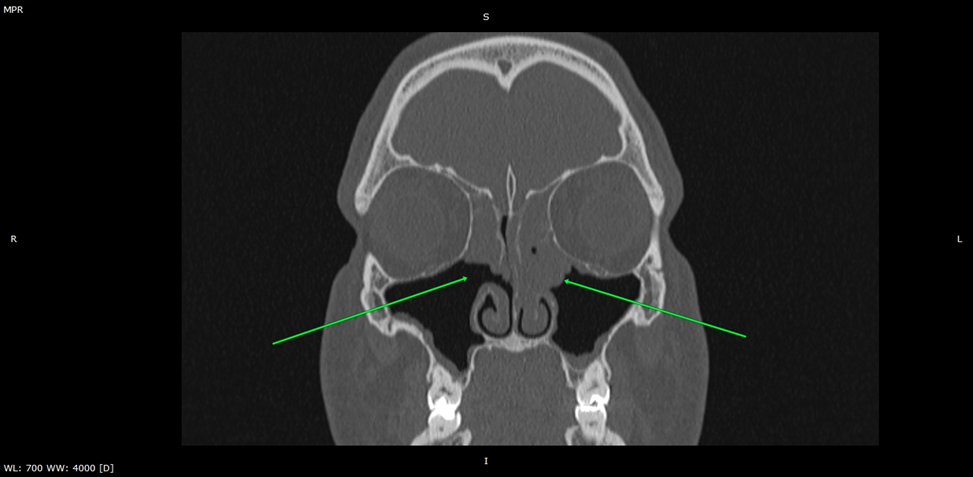

Компьютерная томограмма придаточных пазух носа. Стрелками указаны ячейки решетчатой пазухи, тотально заполненные содержимым.

Ячейки решетчатой пазухи:

тотально заполнены патологическим содержимым, выводные протоки обтурированы.

КТ околоносовых пазух, фронтальный срез. Стрелками указаны утолщенная слизистая оболочка носовых ходов.

Полость носа:

слизистая утолщена с обеих сторон на уровне среднего и верхнего носовых ходов, средние носовые раковины удалены (состояние после операции). Носовая перегородка не искривлена, не имеет дефектов.